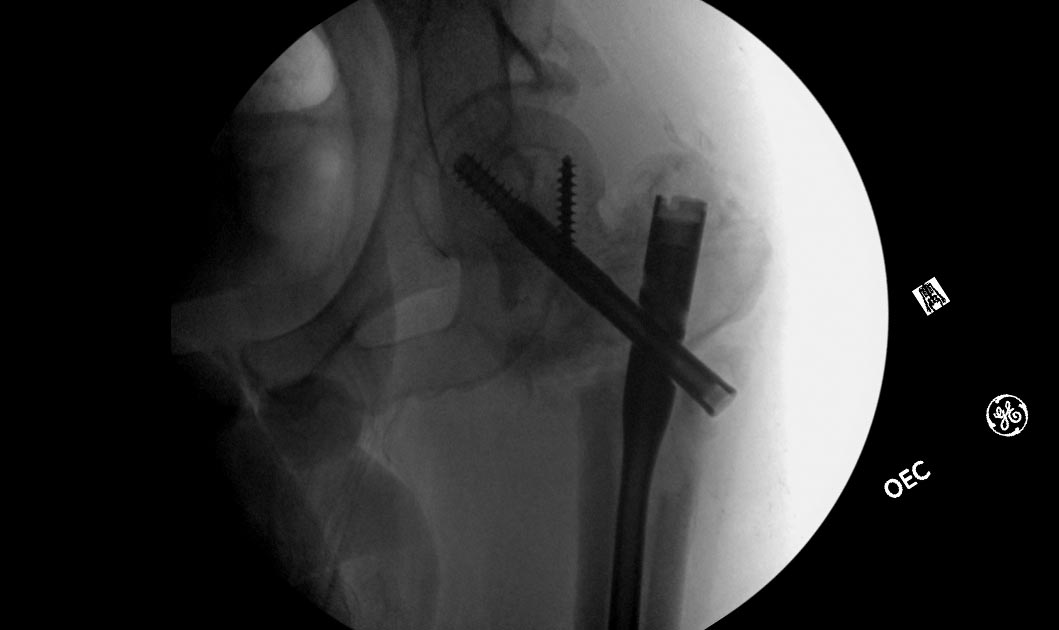

Насчет ревизионного штифтования - вот пример, вчера сделали.